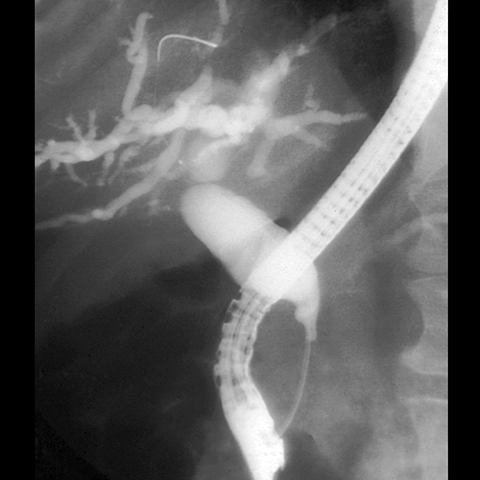

65-year-old male presents with painless jaundice. [5 of 5]